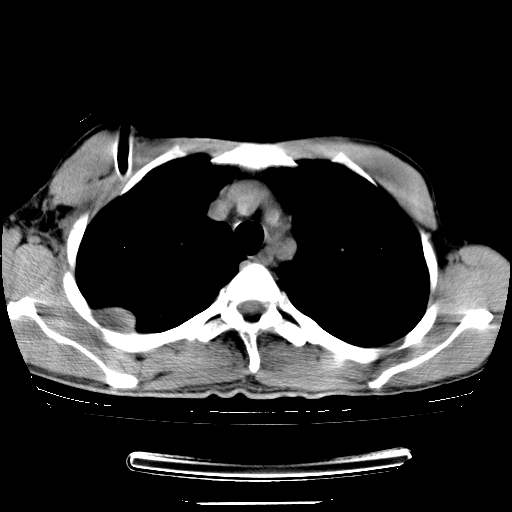

以下是引用dyqct在2008-4-29 8:43:00的发言:[br][br] 支持右侧胸腔包裹性积血。闭式引流管是不是插的太深了?

以下是引用zjzjr在2008-4-29 14:11:00的发言:[br]支持右侧胸腔包裹性积血。闭式引流管是不是插的太深了?胸腔引流,引流管快进入纵隔了.